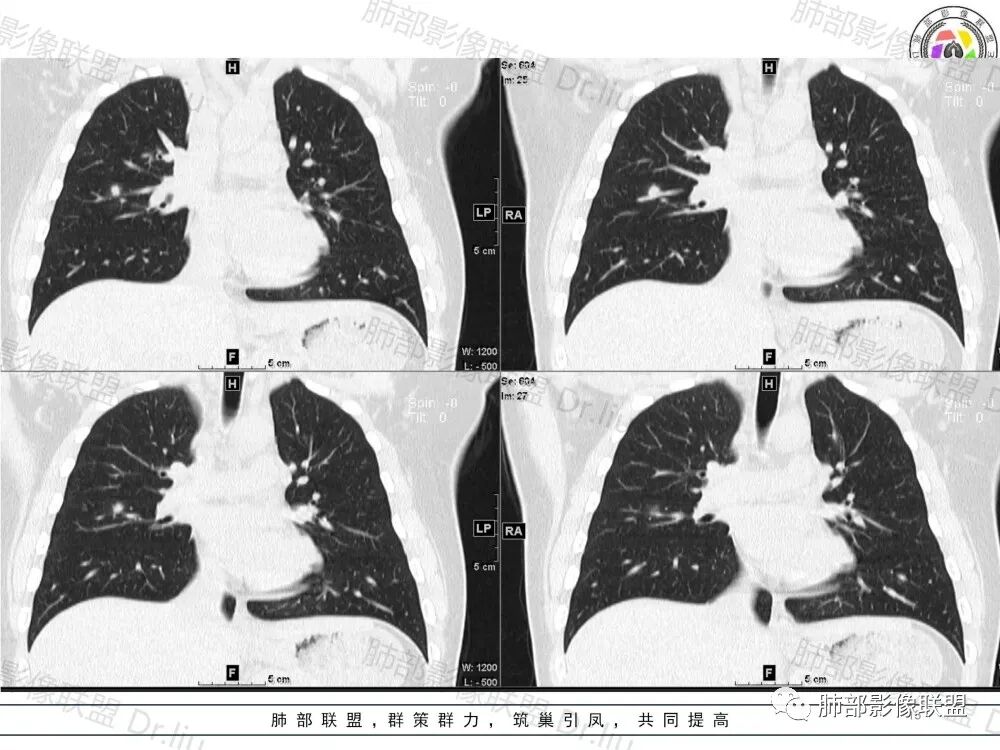

2、影像特点:两肺可见多发大小不一的结节影,部分结节周围可见晕征,部分结节沿着支气管血管束分布,部分位于胸膜下。前纵隔内可见多发结节样软组织密度影,边界不清,部分病灶融合倾向,其脂肪间隙显示模糊。由于腹腔层面少,未能确定腹腔内有无增大淋巴结,需要连续层面追踪观察。

3、病例小结:年轻男性+前纵隔多发结节样软组织影+双肺多发结节,需要警惕淋巴瘤,至于多数老师提到鉴别结节病,结节病以双肺门对称性淋巴结肿大为典型表现,其肺内表现多为沿肺门旁支气管血管周围间质分布的多发结节,结节病可表现纵隔内多发淋巴结肿大、且淋巴结密实,孤立少融合,该病例中均缺乏以上特点,另外结节病好发中青年女性,此病例年龄亦不符合。